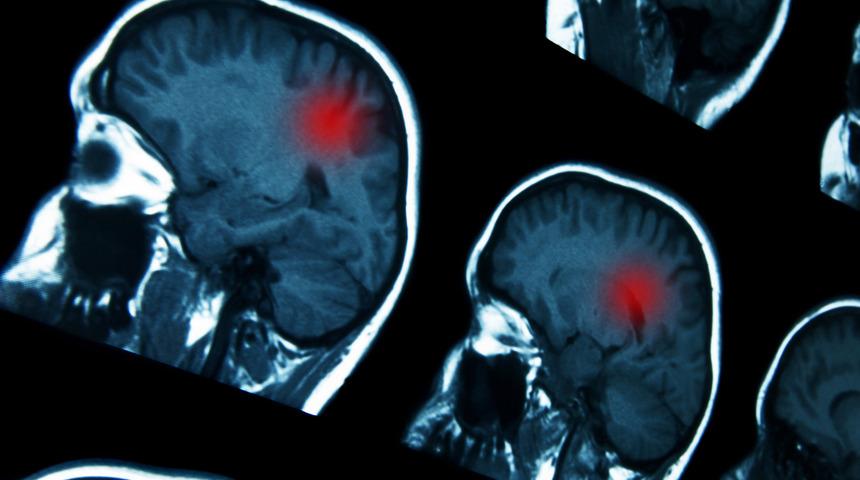

Beyin tümörünün en yaygın belirtisi baş ağrısı!

Beyinde yer kaplayan hastalıklara baktığımızda bunların benign (iyi), malign (kötü) karakterlerde davranış gösterebildiğini söyleyebiliriz. Hastalar kitlenin bulunduğu yer ile ilgili fonksiyonel kayıplarla ve genel şikayetler ile doktora başvururlar. Hastalarda problemin başlamasının ana sebebi; kapalı bir alanda bulunan beyinde yani kafa içinde basıncın artmasıdır. En sık başvuru sebebi baş ağrısıdır. Sonrasında bulantı-kusma, şuur dalgalanmaları, uyku hali, baş dönmesi ve nöbet geçirme, vücudun farklı bölgelerinde kuvvetsizlikler, iştahsızlık, unutkanlık gelmektedir. Ancak şikayetler çok daha çeşitlilik gösterebilir. Hastalarda kitlenin bulunduğu yerin farklılığına göre dengesizlik, çift görme, görememe, yazılanı okuyamama, konuşamama, konuşulanı anlamama, yeni kelimeler ile konuşma, işitme bozuklukları, kulaklarda çınlama, kişilik değişiklikleri görülebilir. Bazılarında ise kafada şişlik, gözde dışarı doğru şişme, yüz felci gibi belirtiler olabilmektedir.